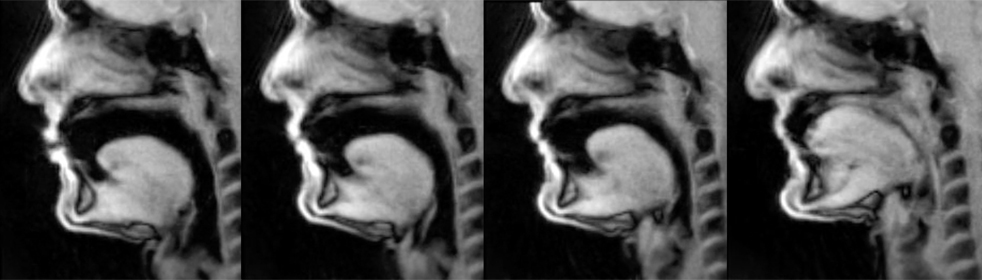

Left to right: pedal B-flat, low B-flat, tuning B-flat, high B-flat

These four images – still screen shots taken from the videos – show four different notes. From left to right, you see me playing and holding a pedal B-flat, low B-flat, tuning B-flat, and high B-flat. As I play successively higher notes, my tongue changes shape. By the high B-flat, my tongue takes up most of the available space in the oral cavity and the oropharynx has constricted as well. Yet the throat and neck remain relaxed. Apart from a slight firming of my chin, my profile is nearly identical on all four notes.

But . . .

There is virtually no change between the images for the pedal B-flat and the low B-flat. For both notes, the shape, size and position of the tongue is almost identical. The oropharynx is slightly more open for the pedal B-flat than for the low B-flat, but this is a very subtle difference. Both notes show a very open oral cavity. What does this mean? First, we see that my approach to playing is generally very stable. While in the scanner, I simply tried to play the way I normally play, despite the constraints imposed by an unfamiliar instrument and mouthpiece, and the need to play lying on my back. I don’t use an embouchure shift for pedal tones, and the pedal tone seems, as I look at these photos and videos, to simply be a lower sounding note than the note above, and one that does not require a radical change in how the note is made. Absent are any embouchure, chin or oral cavity gymnastics to produce the pedal tone. Second, this shows that tongue placement is not always an indicator of pitch production. While some teachers posit that the tongue has no role in pitch production and that embouchure alone determines pitch, that is clearly not true. On the other hand, the nearly identical tongue placement for my pedal B-flat and low B-flat shows that in the case of these two notes, my tongue was not a significant actor in pitch production. Clearly my embouchure had a greater role in determining the pitch of these two notes, and that is evident when you look at my lips. For the pedal B-flat, my lips are more relaxed, and that is the significant factor that allows me to produce and center that note.